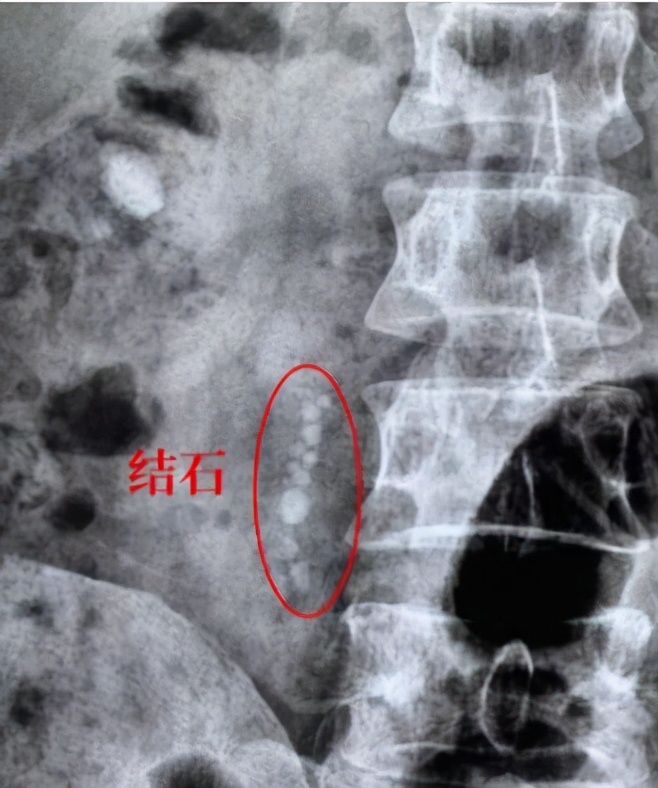

8)石街形成:多数因为较大肾结石碎石后,无法自行排出所有结石,而因为远端输尿管堵塞后,后续碎石堆积而成,会引起疼痛等症状,甚至引起肾积水,影响肾功能,需要进一步治疗(输尿管镜下碎石术等)

体外冲击波碎石术后,因碎石无法排出,堵在输尿管里,形成石街,导致输尿管梗阻,引起肾积水,需进一步治疗